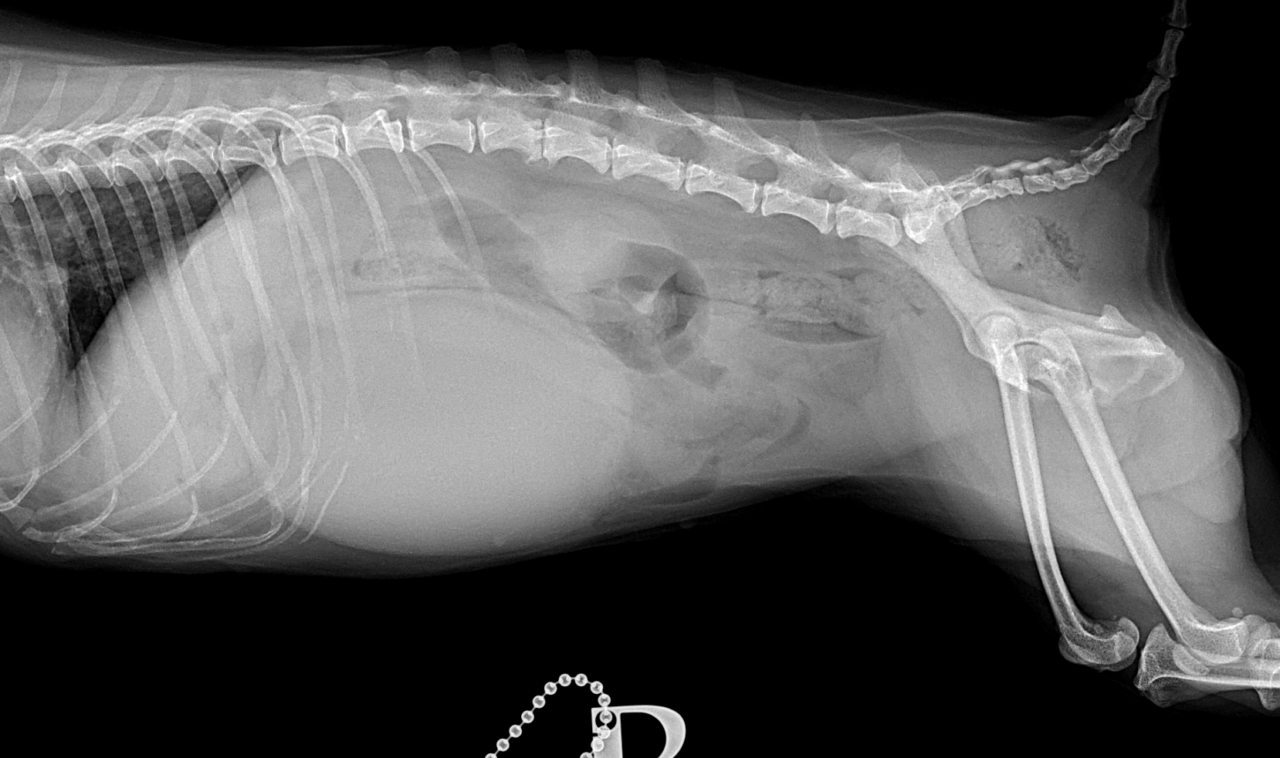

画像診断:特徴的な所見は述べらていませんが、CTで子宮の捻転基部が観察されました。

本症例は子宮水腫に続発した捻転と考えられました。ちいさな体で頑張ってくれました。